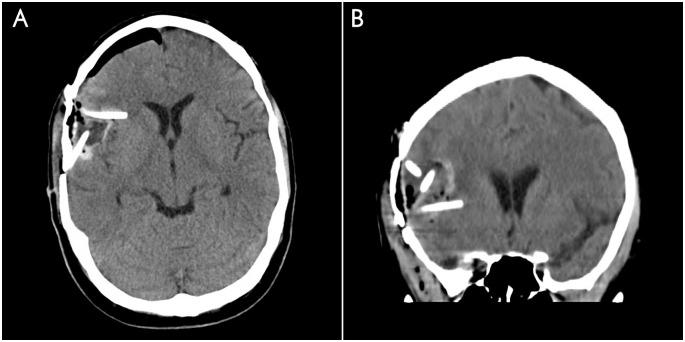

Cohorts of 3 patients with recurrent WHO grade III or IV gliomas were treated with escalating doses of CED carboplatin (1-4 μg in 54mL over 72 hours) delivered via catheters placed at the time of recurrent tumor resection. The primary outcome measure was determination of the maximum tolerated dose (MTD). Secondary outcome measures included overall survival (OS), progression-free survival (PFS), and radiographic correlation.

A total of 10 patients have completed treatment with infusion doses of carboplatin of 1μg, 2μg, and 4μg. The total planned volume of infusion was 54mL for each patient. All patients had previously received surgery and chemoradiation. Histology at treatment include GBM (n = 9) and anaplastic oligodendroglioma (n = 1). Median KPS was 90 (range, 70 to 100) at time of treatment. Median PFS and OS were 2.1 and 9.6 months after completion of CED, respectively. A single adverse event possibly related to treatment was noted (generalized seizure).